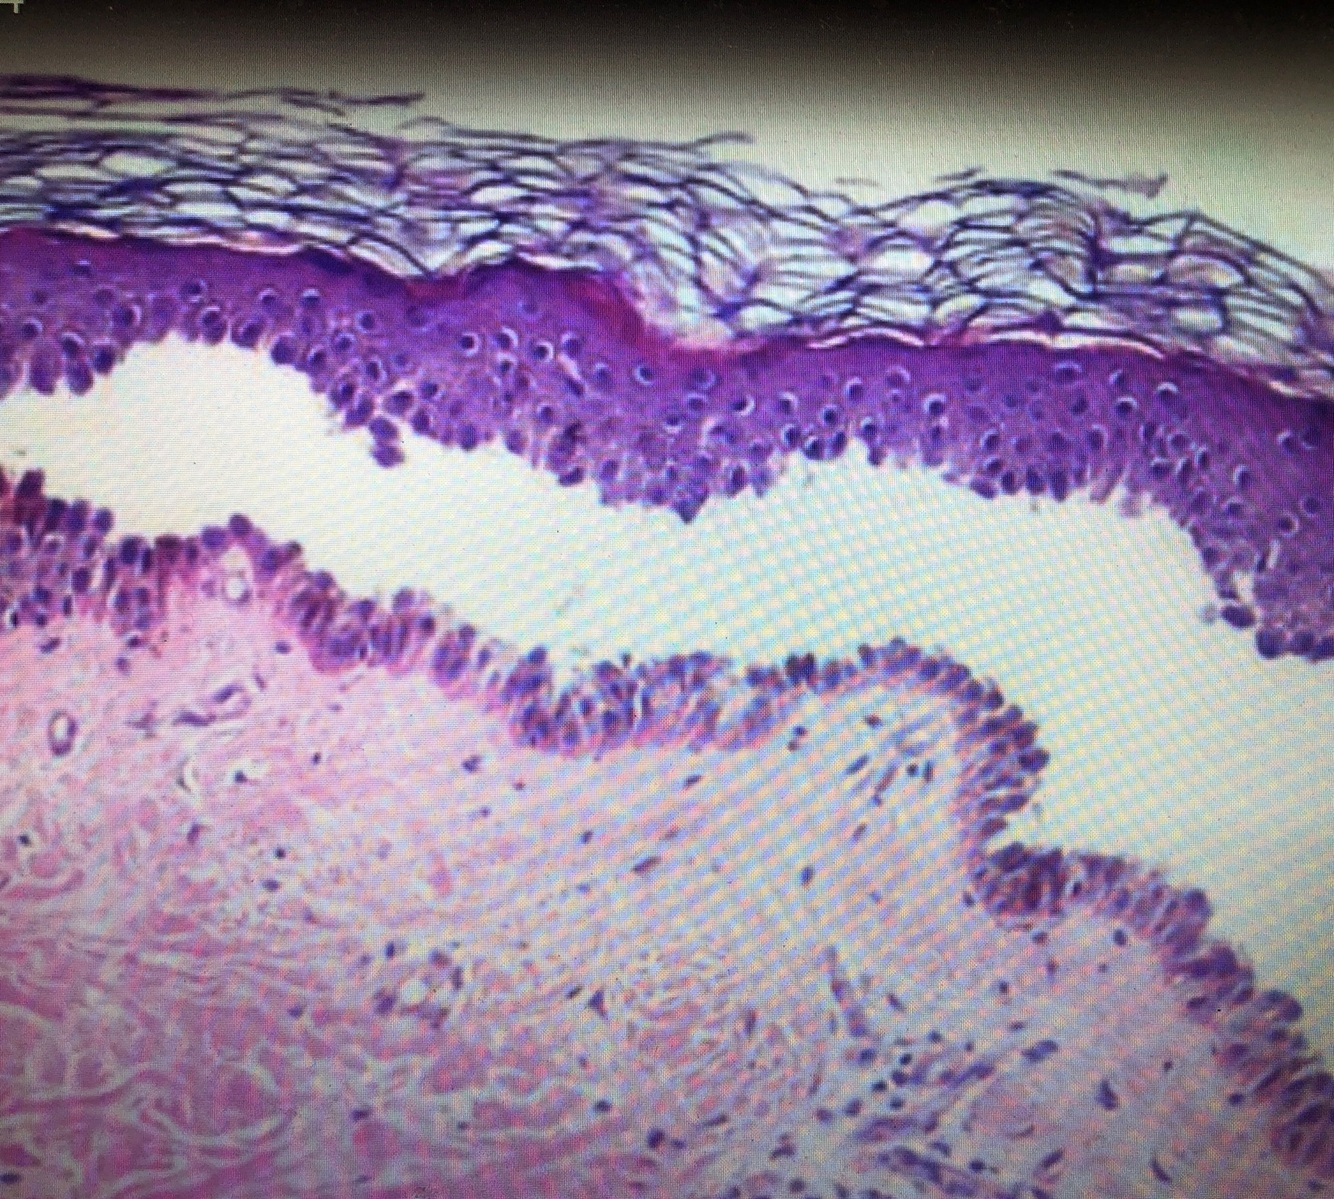

Qual o dx?

Dermatite herpetiforme

- AP: bolha subepidermica com microabscessos de neutrofilos nas papilas dermicas

Tipos de EB

• EB simples

• EB juncional

• EB dermolítica (distrofica)